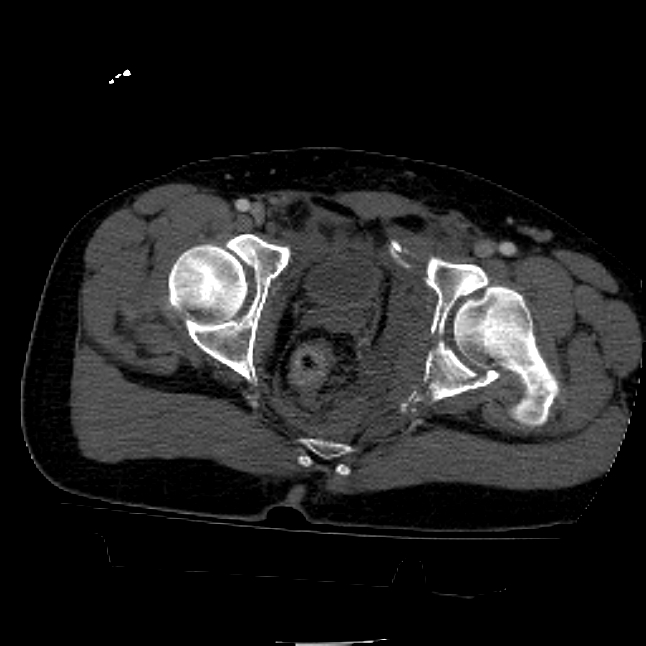

25 yo brittle diabetic, became hypoglycemic and passed out on his motorcycle. Sustained bilateral lateral Hoffa fractures with associated LCL injury on the right and right distal radius fracture. I have questions regarding his pelvic ring/acetabular fracture on the left. Appears to be a very low posterior column fracture with associated posterior wall, marginal impaction. Superior and inferior rami fractures as well on the left giving him a floating segment of inf ramus/ischium/posterior column, but no detectable posterior ring injury. Should the posterior column/posterior wall fracture be addressed surgically because of the marginal impaction? Or is this fracture low enough to be treated non-operatively? I appreciate the input.

I believe the more serious component of the acetabular fracture to be the large (almost 50%) impacted, comminuted zone of the posterior wall. In several series, including the one I reported at the AAOS in 2002 in Dallas of 100 acetabular fractures with posterior wall involvement, all repaired by a single surgeon (Kyle Dickson), those with posterior wall impaction did significantly worse than those without. Nevertheless, the large area of involvement, as well as a joint designed for very low tolerances of "out of round", would indicate that the best chance for avoiding early degenerative changes would be an anatomic repair.

It's an interesting case. The plain films show the impaction, but most of the joint looks pretty good. The CT cuts look awful, though.

The impaction is so big I don't think I would ignore it. It IS down low, but it takes up almost the whole southern hemisphere of his joint.